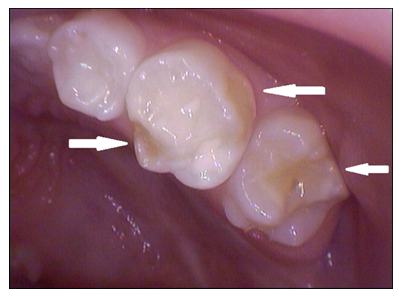

Razvojni defekti se razvijaju i na bočnim zubim i ponekad je i za stručnjaka teško da ih primeti.(slika 6.). Na ovakve defekte se često nadovezuje karijes. Slična pojava je karakterističnija za stalne zube i zahvata sekutiće i prve kutnjake(“šestice”) i naziva se MIH(Molarno sekutćna hipomineralizacija).

Slika 5. Razvojni defekt gleđi na bočnim mlečnim zubima koji se teško uočavaju i često brkaju sa karijesom.